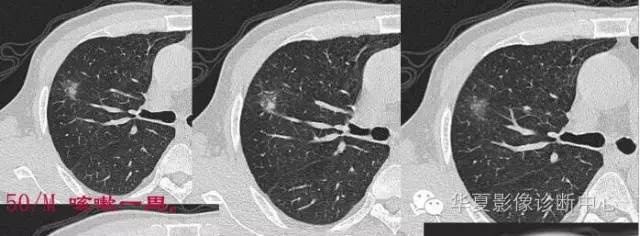

这一例是否GGO成分几乎没有

基本是实性的

那就按实性的分析

磨玻璃结节良恶性影像分析策略 都是支气管

胸膜凹陷,分叶征